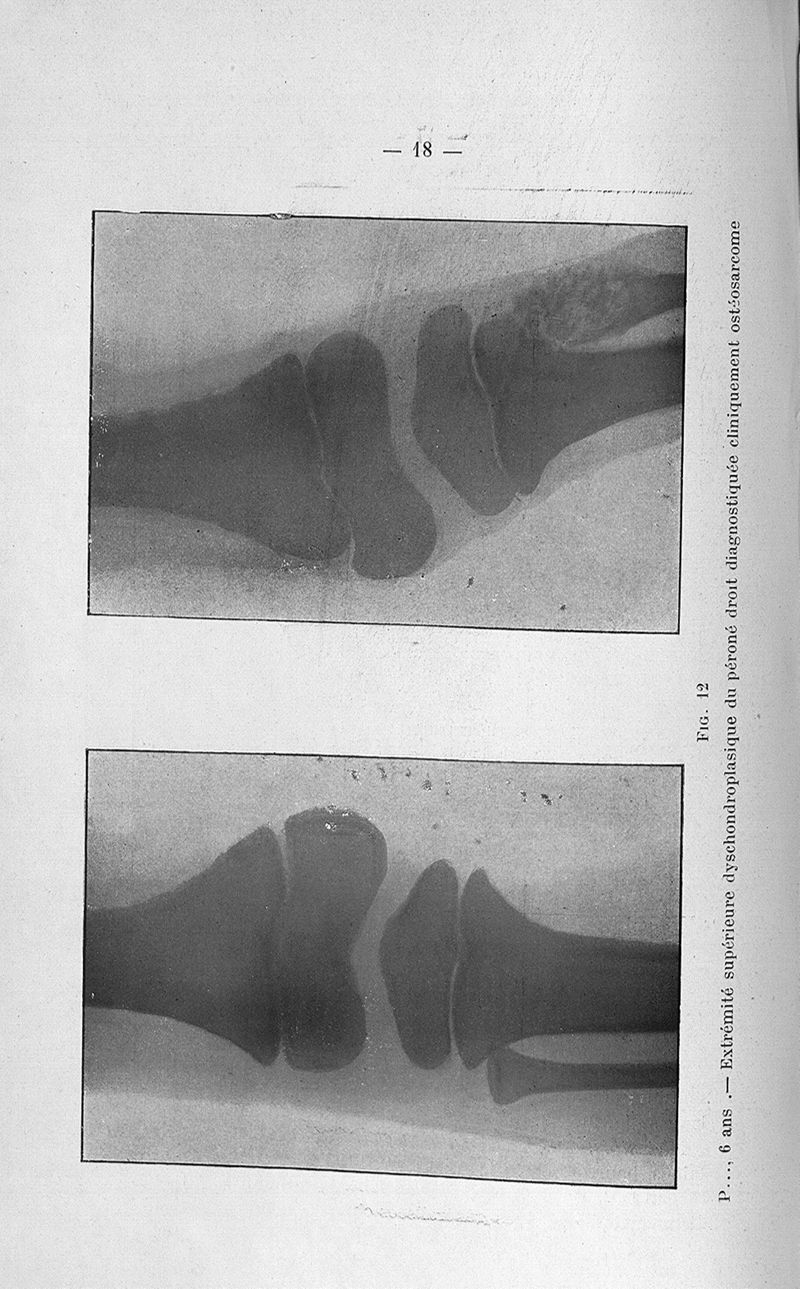

Concours pour l'agrégation, 1904, section de chirurgie et accouchements. Titres et travaux scientifiques